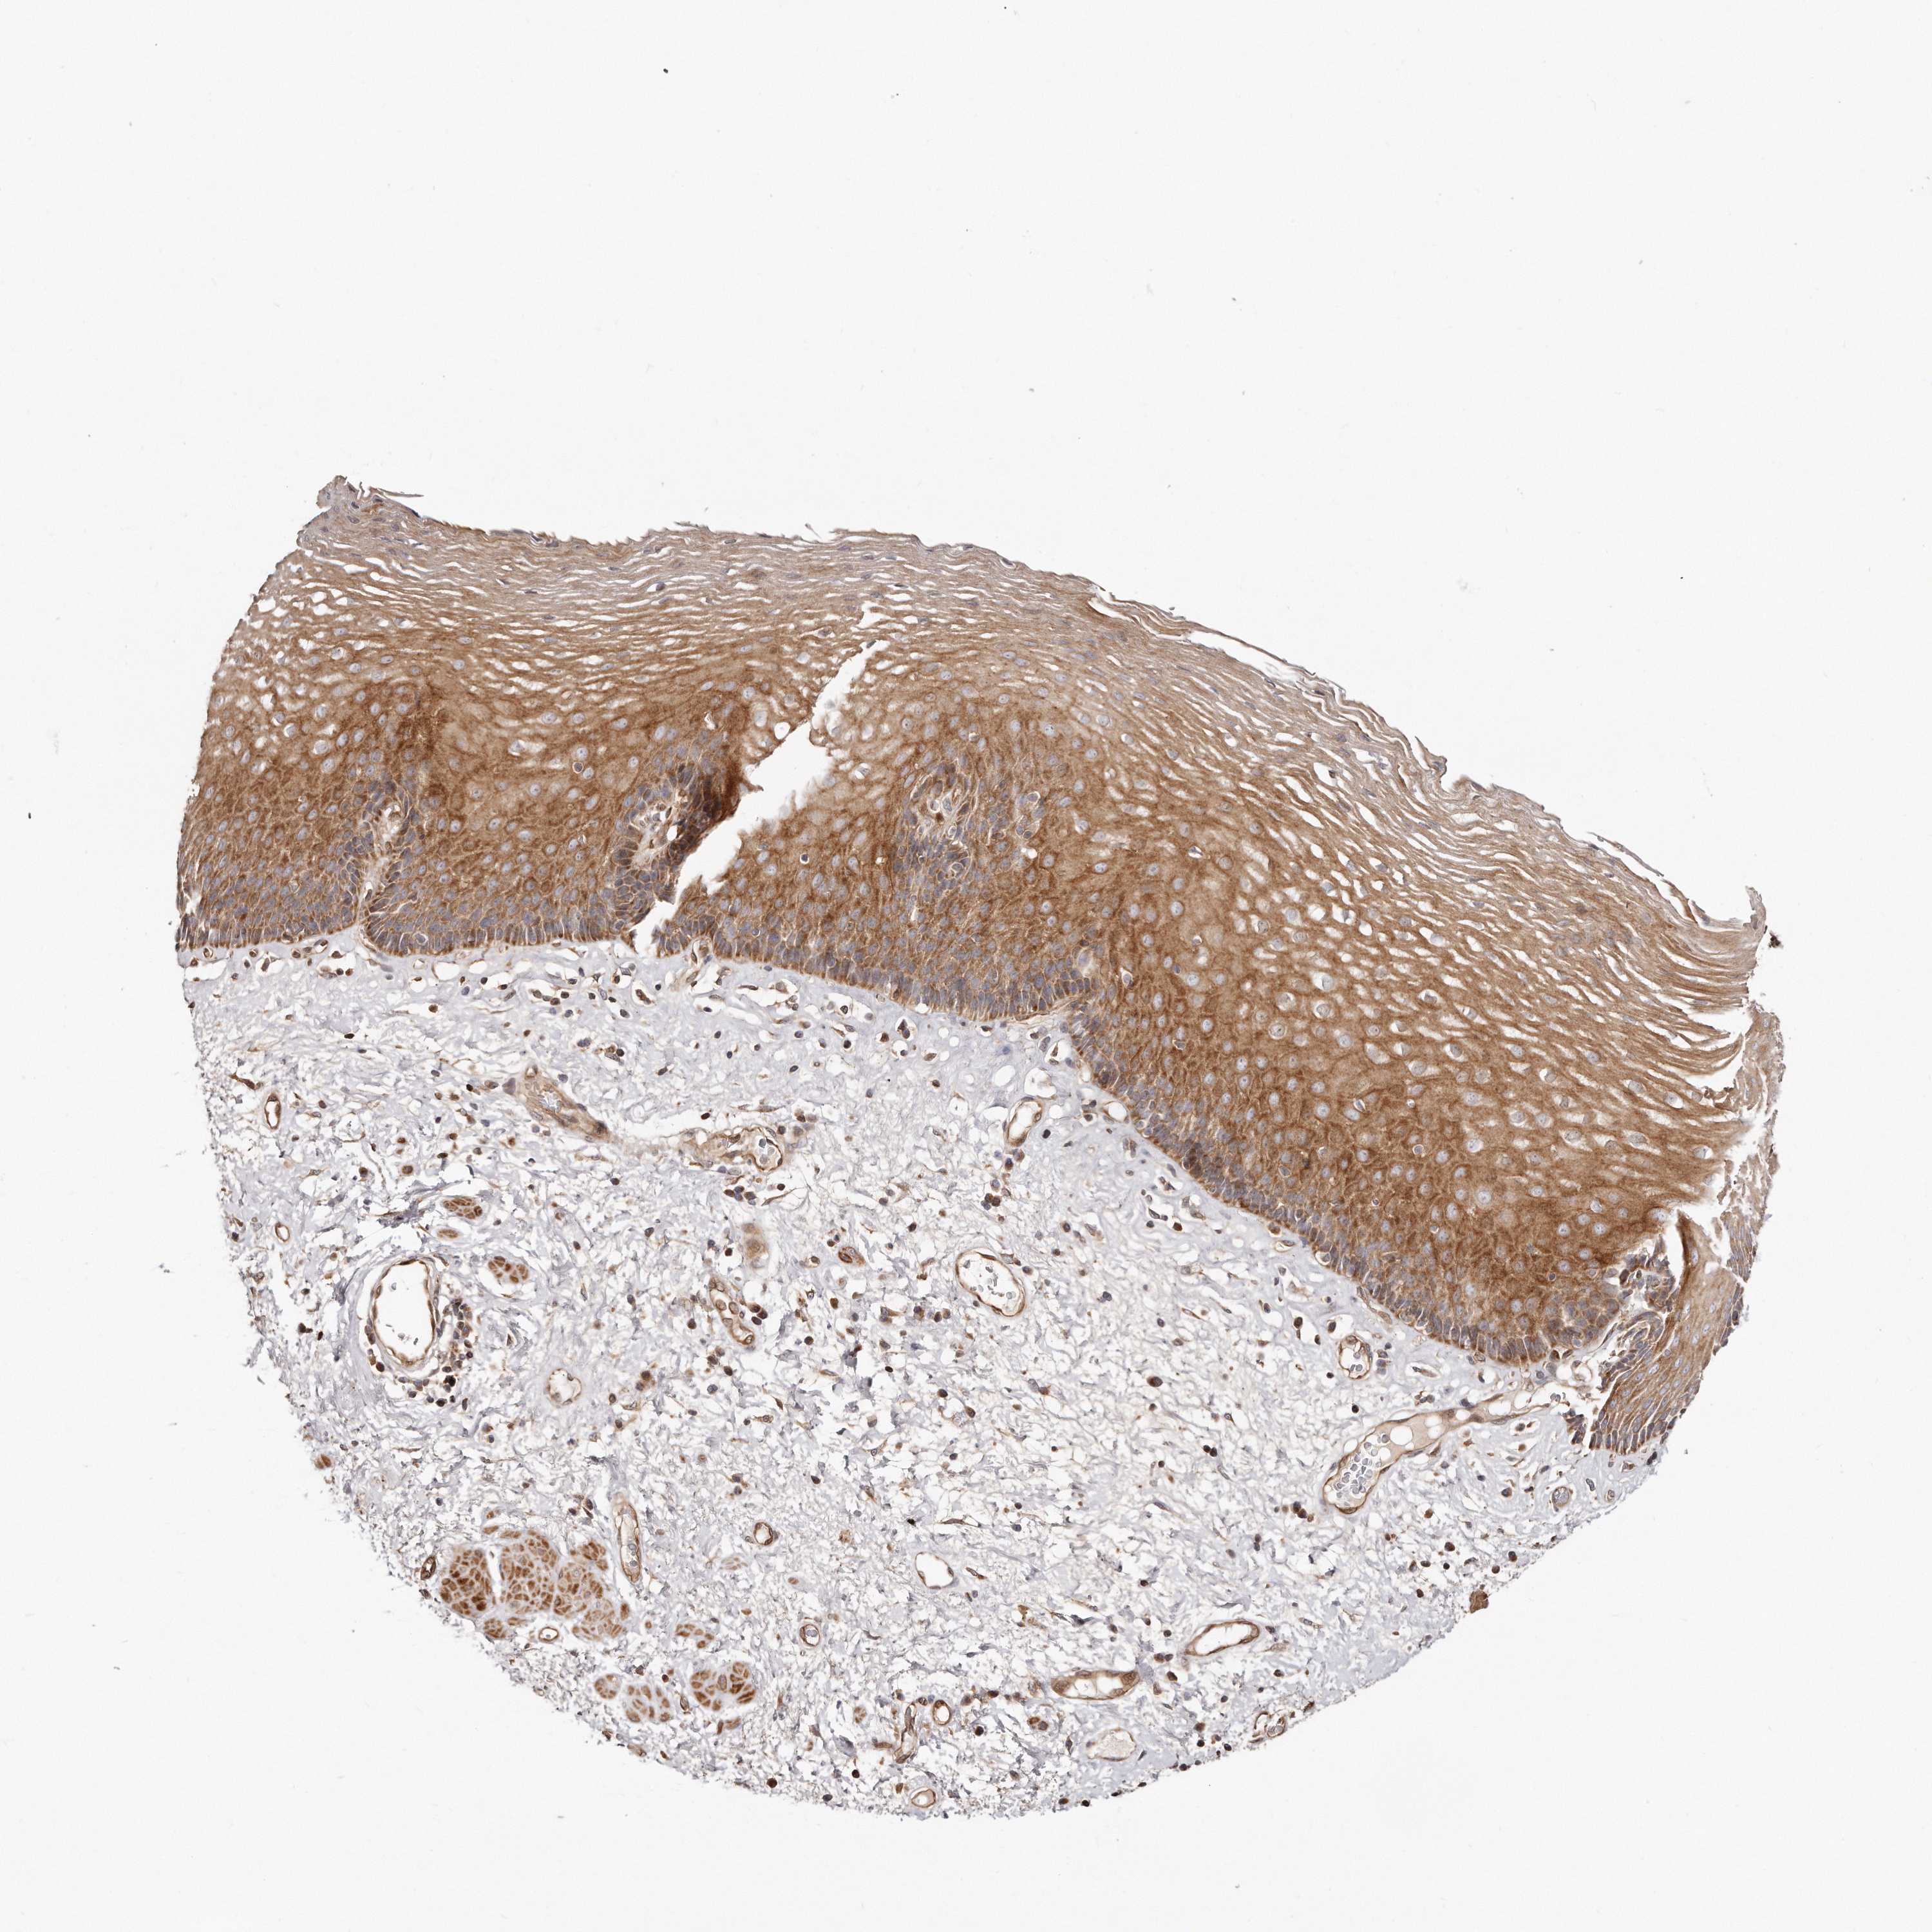

ESOPHAGUS - Antibody stainingi

Antibody staining in the annotated cell types in the current human tissue is reported as not detected, low, medium, or high, based on conventional immunohistochemistry profiling in selected tissues. This score is based on the combination of the staining intensity and fraction of stained cells.

Each image is clickable and will lead to virtual microscopy that enables deeper exploration of all samples and also displays staining intensity scores, fraction scores and subcellular localization as well as patient and tissue information for each sample.

Antibody HPA030101

Squamous epithelial cells Medium